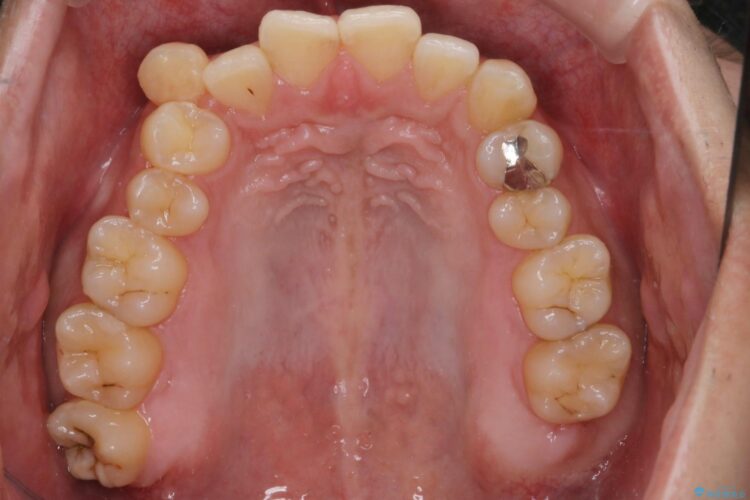

上の八重歯と下の歯のがたつきが気になるとご来院された患者様です。

精密検査の結果、抜歯の必要はないと判断しました。臼歯を遠心移動させ、歯列をワイヤーで整えることでスペースを確保し、IPR(歯と歯の間を削る処置)を加えて歯並びを綺麗にする治療計画を立てました。